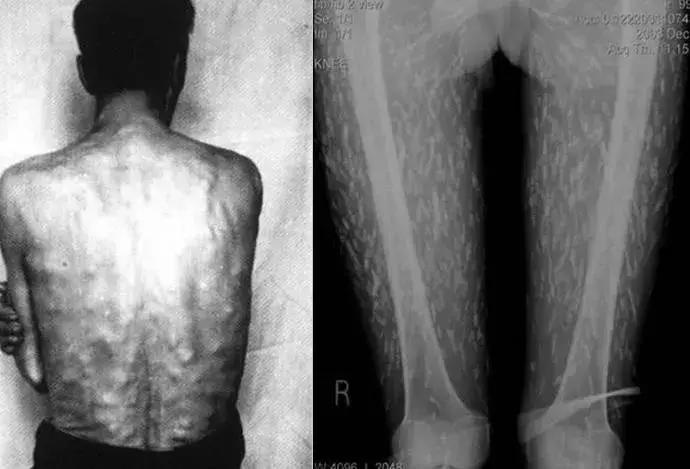

以绦虫为例。幼虫会通过人体循环,进入各组织器官发育为囊虫,最后演化成囊虫病。

如果囊虫入侵到了眼睛部位,轻则产生眼部炎症,重则失明!

最严重最常见的还是脑囊虫病,占了囊虫病的80%。囊虫进入到脑部,首先会压迫脑组织,造成炎症、水肿等。严重会使人产生明显的神经障碍,甚至死亡。

点状物即为囊虫